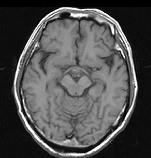

问题 男,头痛7月余,伴左侧面部麻木,疼痛剧烈时伴恶心,无呕吐,请根据所提供图像,选择最可能的诊断()

选项 A.垂体瘤 B.颅咽管瘤 C.生殖细胞瘤 D.脑膜瘤 E.胶质瘤

答案 B